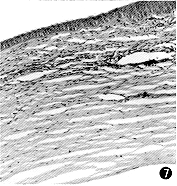

图7 CDI治疗Ⅰ组第12天,角膜组织中有炎性细胞浸润,无明显新生血管增生 HE×115

图8 CDI治疗Ⅱ组第12天,角膜组织内有少量管径较细的新生血管在层间增生,亦有炎性细胞聚集 HE×115